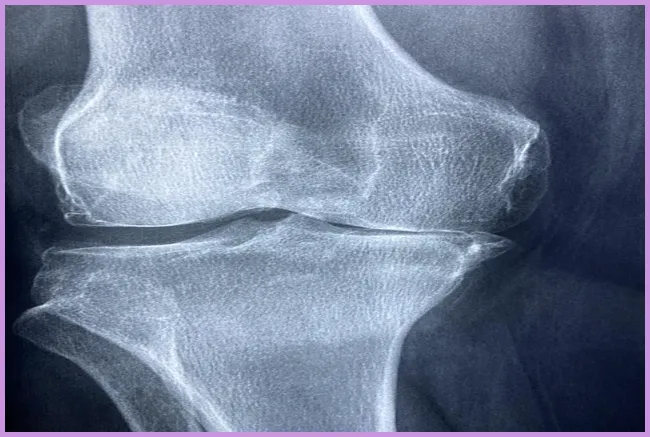

어깨 통증이 지속되면 어떤 검사를 받아야 하나요?

어깨 통증이 3주 이상 지속될 경우, 정형외과 전문의를 방문하여 엑스레이, MRI 또는 초음파 검사를 통해 정확한 진단을 받는 것이 중요합니다. 이를 통해 통증의 원인을 파악하고 적절한 치료 계획을 세울 수 있습니다.